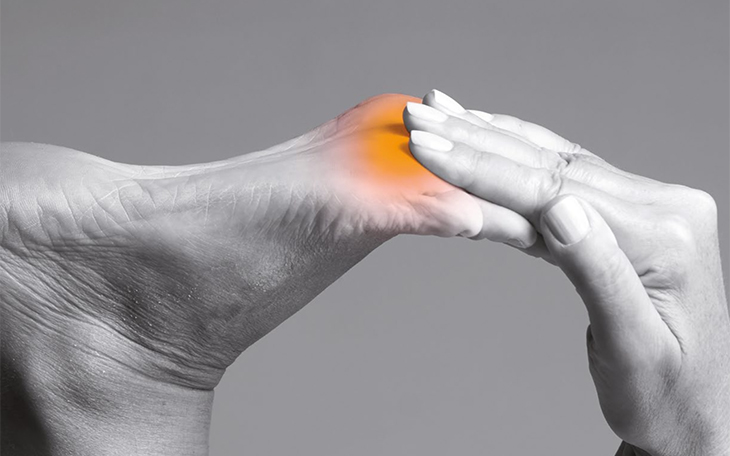

Symptome

Typisch sind Schmerzen im Bereich der Achillessehne, die sich bei Belastung verstärken. Oft treten die Schmerzen morgens oder nach längeren Ruhephasen auf (Anlaufschmerz). Auch eine Schwellung und Überwärmung im Bereich der Sehne können auftreten.

Ursachen

Häufige Ursachen sind Überlastung, falsches Schuhwerk, eine verkürzte Wadenmuskulatur, Fußfehlstellungen oder auch eine unzureichende Aufwärmung vor dem Sport.

Konservative Therapie

Entlastung, Kühlung, Dehnübungen der Wadenmuskulatur, Fersenerhöhung, entzündungshemmende Medikamente, Physiotherapie und Stoßwellentherapie können die Beschwerden lindern.

Operative Therapie

Wenn die konservativen Maßnahmen nicht ausreichend helfen, kann eine Operation in Erwägung gezogen werden. Dabei wird das entzündete Gewebe entfernt und die Sehne gegebenenfalls rekonstruiert.